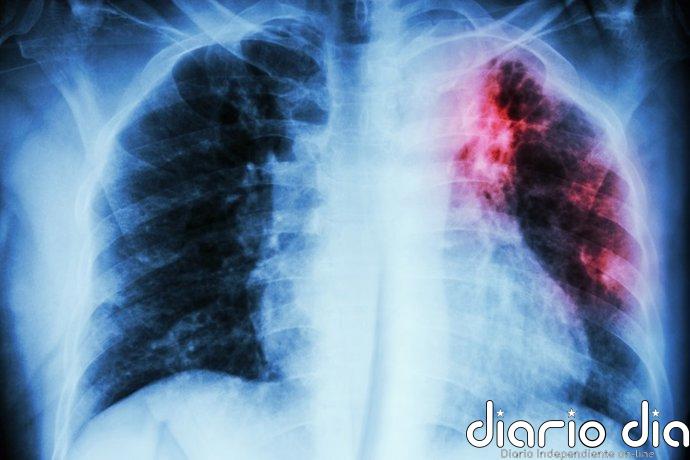

La fibrosis quística se puede detectar en las primeras semanas de vida con el cribado neonatal, situación que facilita una intervención temprana que mejora significativamente la evolución de las personas con esta enfermedad. Sin embargo, el acceso a pruebas diagnósticas, a una atención especializada y a otros recursos sanitarios «sigue siendo desigual según la comunidad autónoma».